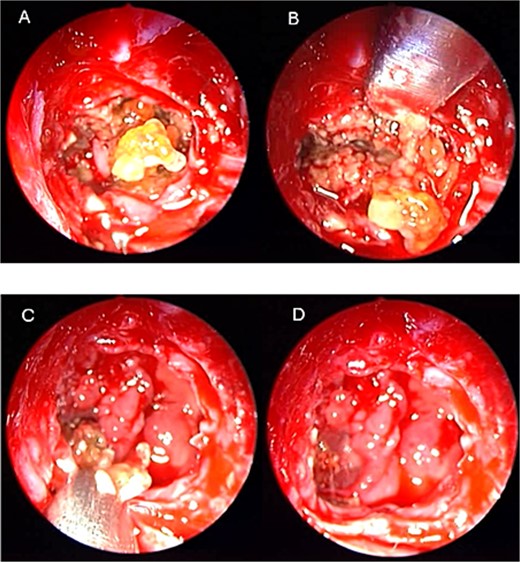

An asthmatic 42-years-old patient who was previously medically treated for allergic rhinitis with no significant improvement. A subsequent CT scan revealed isolated sphenoid sinus disease (Fig. 3). Intra-operative endoscopic findings revealed fungal mud and mucin (Fig. 4A and B) with post-operative (Fig. 4C) endoscopic finding of widely open, clean sphenoid sinus. Further histological examination of the specimen proved the diagnosis of eosinophilic AFS.

Coronal CT scan image showing complete sphenoid sinus heterogenous opacification.

Intra-operative (a, b, and c) endoscopic sphenoidotomy showing mud and mucin, with post-operative examination (d) of right optico-carotid recess showing wide and clean sphenoid sinus.